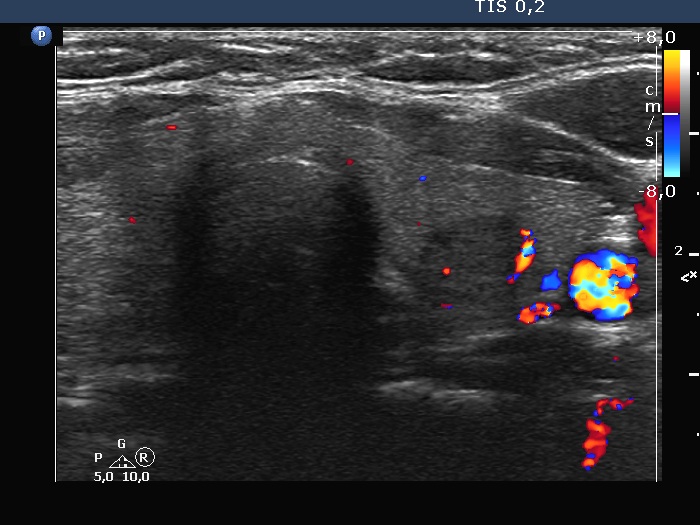

Left lobe, transverse scan, color Doppler mode. A relatively large vessel runs at the lateral part of the lesion.